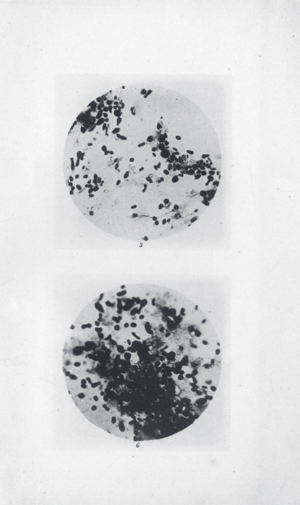

Oriental rat flea (Xenopsylla cheopis) infected with the Y. pestis bacterium, which appears as a dark mass in the gut: The foregut (proventriculus) of this flea is blocked by a Y. pestis biofilm; when the flea attempts to feed on an uninfected host, Y. pestis is regurgitated into the wound, causing infection.

Y. pestis isolated by Ricardo Jorge (pt) during the 1899 Porto plague outbreak

In 1894, two bacteriologists, Alexandre Yersin of Switzerland and Kitasato Shibasaburō of Japan, independently isolated in Hong Kong the bacterium responsible for the Third Pandemic. Though both investigators reported their findings, a series of confusing and contradictory statements by Kitasato eventually led to the acceptance of Yersin as the primary discoverer of the organism. Yersin named it Pasteurella pestis in honor of the Pasteur Institute, where he worked. In 1967, it was moved to a new genus and renamed Yersinia pestis in his honor. Yersin also noted that rats were affected by plague not only during plague epidemics, but also often preceding such epidemics in humans and that plague was regarded by many locals as a disease of rats; villagers in China and India asserted that when large numbers of rats were found dead, plague outbreaks soon followed.[بحاجة لمصدر]